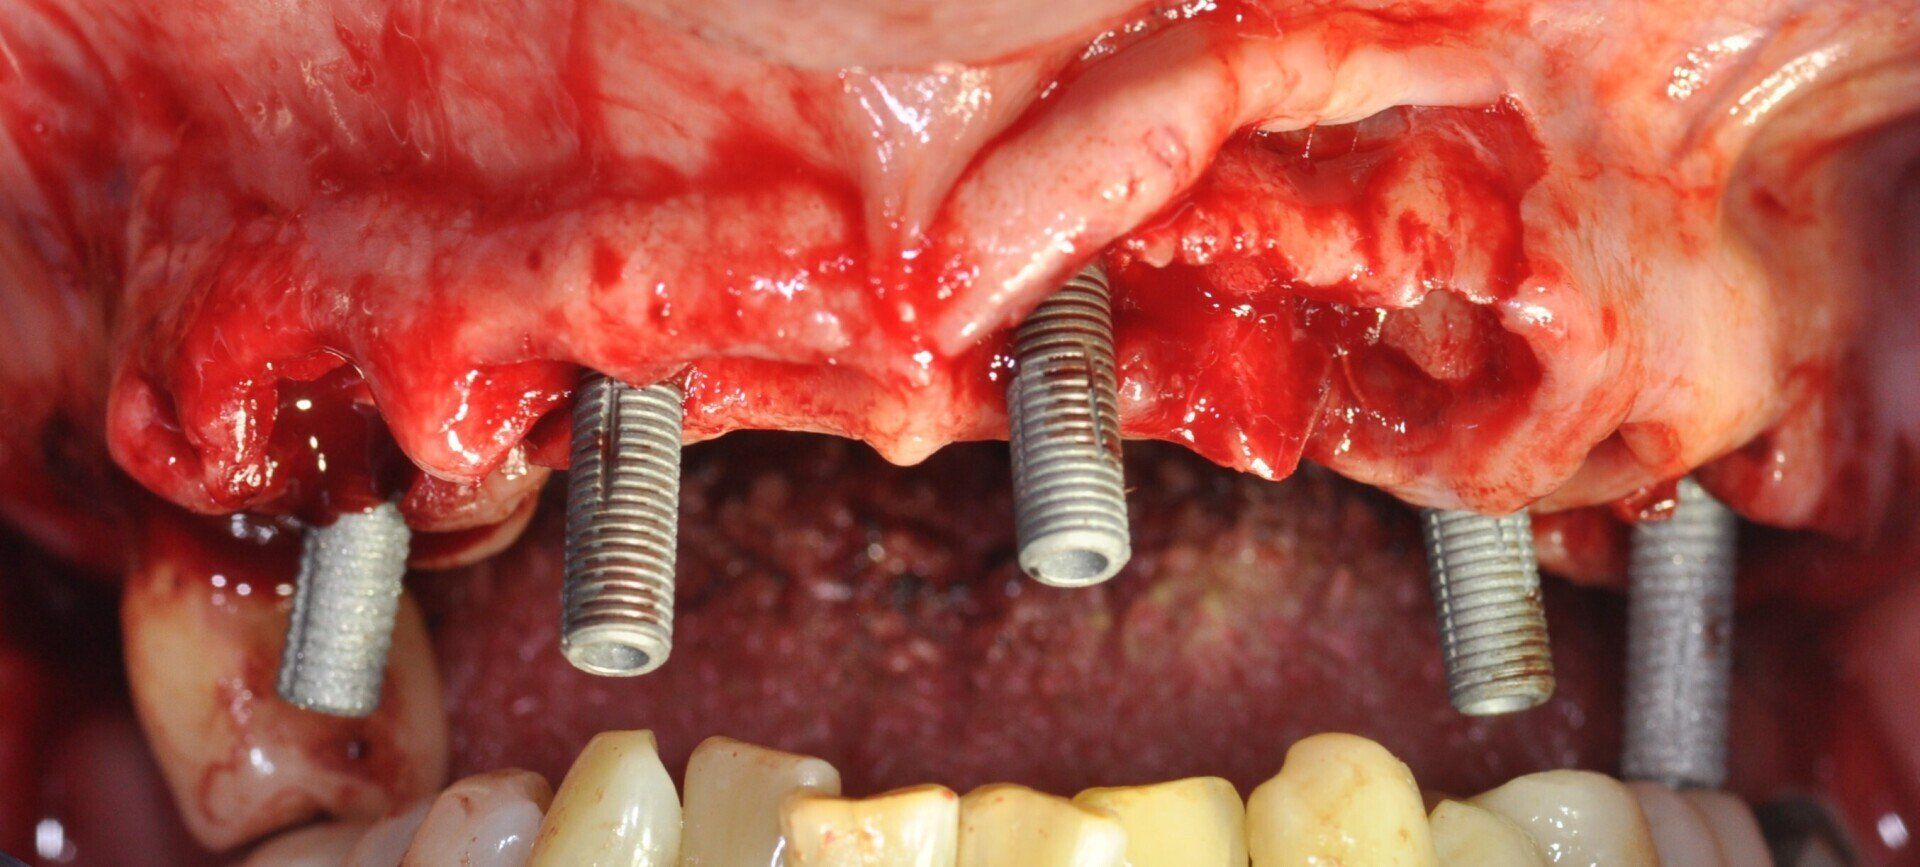

Tutti i pazienti sono stati trattati con tecnica FoB su almeno 5 impianti con superficie Ossean (Intra-Lock, Boca-Raton, FL, USA) raggiungendo un torque non inferiore a 35 Ncm (Fig. 3). Gli impianti in questione presentano una superficie nano-irruvidita con Calcio e una macro-geometria che ben si adatta al carico immediato15, 16. In particolare, il disegno conico facilita l’ottenimento della stabilità primaria ed è stata associata a una osseointergazione precoce della fixture nelle prime settimane17.

Fig. 3_Foto intra-orale durante il posizionamento degli impianti nell’arcata superiore.